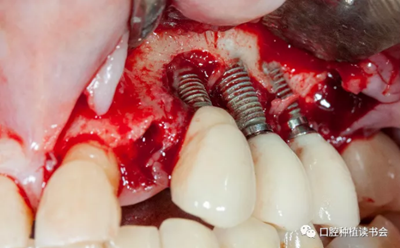

首先去除了螺絲固位的牙冠,引流膿液,翻全厚瓣暴露受感染部位的種植體。對暴露種植體進行種植體成形術(shù),金剛砂車針磨除種植體表面凹槽(圖 20)。

圖20 種植體周圍有膿液滲出,翻瓣后行種植體成形術(shù)